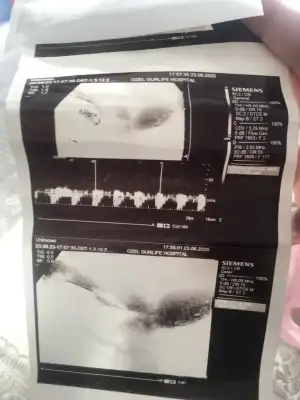

Kizlar merhaba 18haftalik gebeyim.dorduncu kez sormama ragmen doktorum cinsieti hakkinda asla kesin konuşmuyor özele gidiyorum.ister istemez uzuluyorum merak ediyorum her anne gibi haliyle...ultrason cihazida cok eski bebegi cektim diye bobregimi cekip veriyor sanki.Allahtan esim videoya almista ordan bi ss aldim.size atsam tecrubeli anneler tahmin edebilir misiniz?